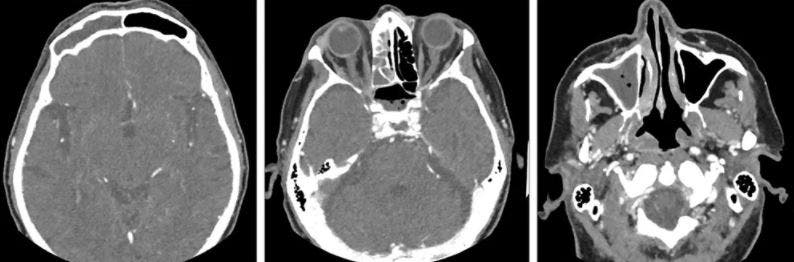

يقول كونور: “كنت أشعر بالألم” ، وكان لديّ مشاكل في الأذن ومشاكل في الجيوب الأنفية حيث شعرت وكأن هناك بالوناً يتم تفجيره في وجهي ، وربما كان هذا هو أسوأ الأعراض. لقد أزعجني حقًا”.